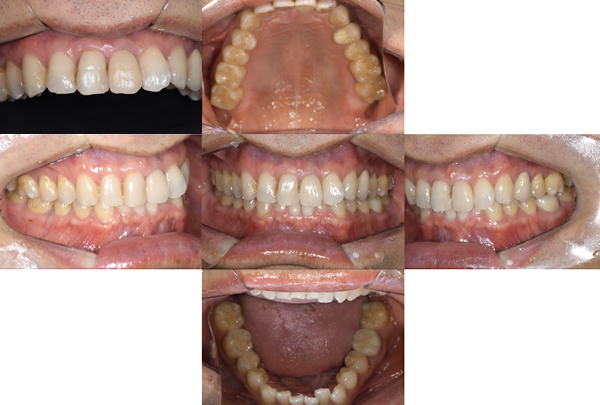

治療内容

口腔内の銀歯を全てセラミックにしたいというご希望でした。親知らずは抜歯しています。笑ったときや自然なスマイルをしたときも銀歯が見えなくなり自然になりました。

治療期間 約2ヶ月

治療費 合計:935,000円 (内訳)

オールセラミック:110,000円×5本

セラミックインレー:55,000円×7本

治療のリスク・副作用 銀歯の下で虫歯が大きくなっていたら歯の中の神経をとらないといけないことがあります。また、被せ物を外すと、ご自身の歯が少ない場合は別途はを残すための処置が必要になることがあります。